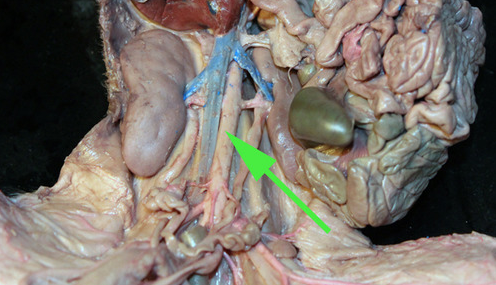

The vein marked by the green arrow is a renal vein

The vessel marked by the green arrow is a renal

artery.